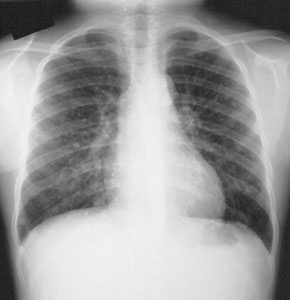

The most common site for distant metastatic disease is the lung [22]. Overall, men have a higher incidence of pulmonary mets. Between 50-60% of metastatic pulmonary lesions will concentrate radioiodine [6]. Patients with iodine concentrating pulmonary metastases have a 5-year survival rate of 60% compared to 30% for tumors which do not concentrate radioiodine [13]. The early (pre-radiographic) scintigraphic diagnosis and I-131 therapy of lung mets appears to be the most important element in obtaining both a significant improvement in survival rate and a prolonged disease free time interval in these patients. In patients with a negative CXR, but positive I-131 scans, there was a 10 year survival rate of 96% and a complete disease remission rate of 80% following I-131 therapy. In patients with both a positive CXR and a positive I-131 scan, the 10 year survival rate was significantly lower (40%) and complete remission was rarely achieved (4%). Patients with a positive CXR, but a negative I-131 scan had the worst prognosis with a 10 year survival rate of only 10% and no complete remissions. In summary- the presence of iodine concentrating pulmonary mets with a negative CXR appears not to influence mortality, however, non-concentrating micro- or macronodular mets do increase mortality risk.

Pulmonary metastases may appear on CT as micronodules (less than 5 mm), macronodules, or the lesions may be radiographically occult and only identified following I-131 imaging or treatment [22]. The micronodular pattern (miliary) of lung mets is invariably related to good I-131 uptake and a better prognosis, while macronodular (over 0.5 cm) mets frequently showed poor uptake and had an associated worse prognosis (fatal outcome was almost always observed in patients with macronodular mets and no I-131 accumulation). Reported 5 year survival rates are 100% for CT occult disease, 88% for micronodules, and 25% for macronodules [22].

Diffuse lung metastases: The patient was an 8 year old female with thyroid cancer. The I-131 exam demonstrated diffuse pulmonary tracer accumulation consistent with metastatic disease. The CXR demonstrated multiple small pulmonary nodules (Click CXR to enlarge image) |